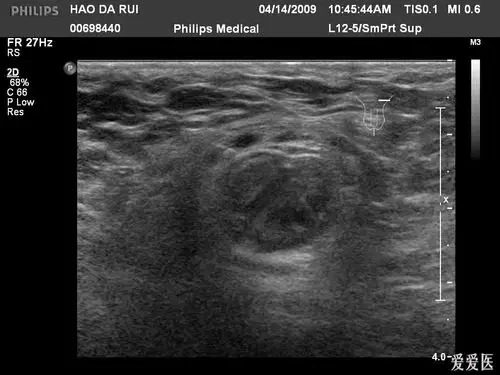

右侧股疝并嵌顿图片 - 超声医学讨论版 - 爱爱医医学论坛

图 1 -图 3:超声检查可见小肠疝出,其周围可见积液,疝出肠管可见血流

股疝嵌顿体表超声图